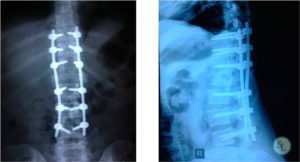

Для стабилизации деформированных позвоночных сегментов проводится операция, во время которой на позвоночный столб крепятся титановые пластины или другие металлоконструкции.

- Транспедикулярная стабилизация. С помощью специальной ножки (педикулы) в смежные позвоночные тела вставляется корригирующая металлическая конструкция в виде винтов, крепко соединенных между собой штангами. Подобная техника чаще всего применяется при смещении или переломе позвонков.

Техника стабилизации поврежденных позвонков подбирается специалистом в индивидуальном порядке, учитывая множество факторов: тип повреждения, возраст и состояние здоровья пациента, наличие противопоказаний. Для операции могут применяться различные металлоконструкции: винты, пластины, стержни, скобы.

На протезированном уровне производится транспедикулярное закрепление позвонков спицами, винтами, пластинами.